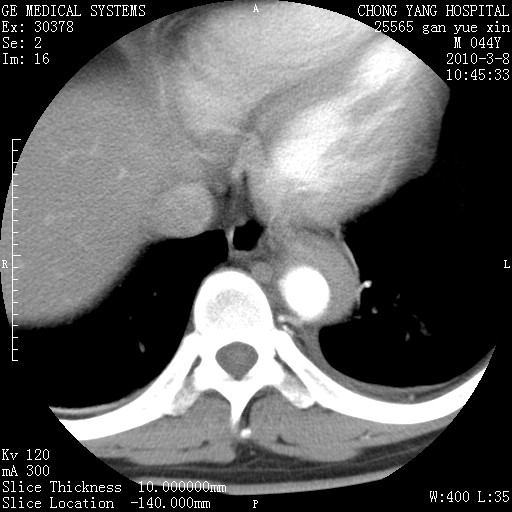

标题: CT24940:主动脉增强,典型病例。 [打印本页]

标题: CT24940:主动脉增强,典型病例。

夹层动脉瘤。

动脉夹层

夹层动脉瘤,典型

主动脉夹层。

动脉夹层的分型:

⒈debakey分型:根据主动脉夹层累及部位,分为三型:ⅰ型:原发破口位于升主动脉或主动脉弓部,夹层累及升主动脉、主动脉弓部、胸主动脉、腹主动脉大部或全部,少数可累及髂动脉。ⅱ型:原发破口位于升主动脉,夹层累及升主动脉,少数可累及部分主动脉弓。ⅲ型:原发破口位于左锁骨下动脉开口远端,根据夹层累及范围又分为ⅲa,ⅲb。ⅲa型:夹层累及胸主动脉。ⅲb型:夹层累及升主动脉、腹主动脉大部或全部。少数可累及髂动脉。

⒉stanford分型:a型:夹层累及升主动脉,无论远端范围如何。b型:夹层累及左锁骨下动脉开口以远的降主动脉。

夹层动脉瘤,少量胸水

夹层动脉瘤;左侧少量胸腔积液。

典型主动脉夹层。